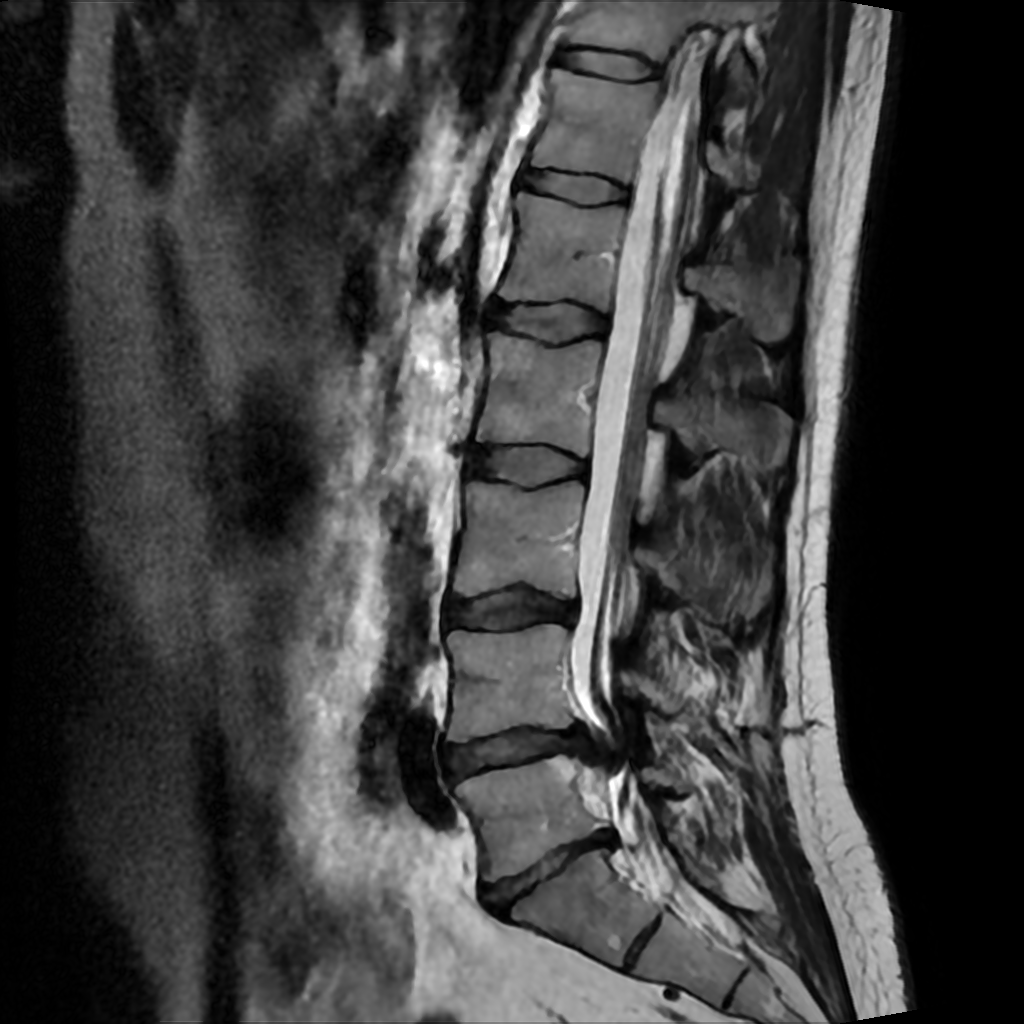

IMG-20251124-WA[...].jpg 107Кб, 819x903

1000016010.png 376Кб, 433x577

1000016009.png 400Кб, 433x577

1000016008.png 393Кб, 433x577

И так.

У меня грыжа диска!!!

И МРТ моё!

MMRLANDRYGGMR20[...].png 982Кб, 1024x1024

Хуйня у тебя, а не грыжа. Зацени мою:

L5 / L5 11 мм. Осенью боль была такая, что аж морфин прописывали и тот не до конца снимал. Теперь мне упражнения всю жизнь делать. Если все окей, то войду в ремиссию и опять буду и на веле и на лыжах горных катать. А пока работаю большую часть дня стоя, чтобы спину не нагружать. Хорошо, что и в офисе и дома столы с электро лифтом